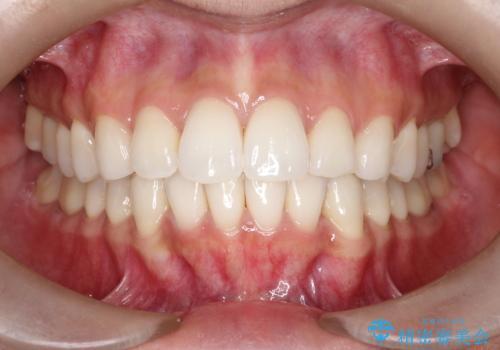

神経を抜かずに守る。MTAを用いた部分的断髄法と精密セラミック修復

前歯の気になる変色を解消。再根管治療とオールセラミックで自然な美しさへ

担当医 河口智英